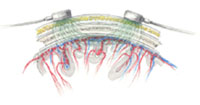

Perfusion of the brain: Path of light through the

head